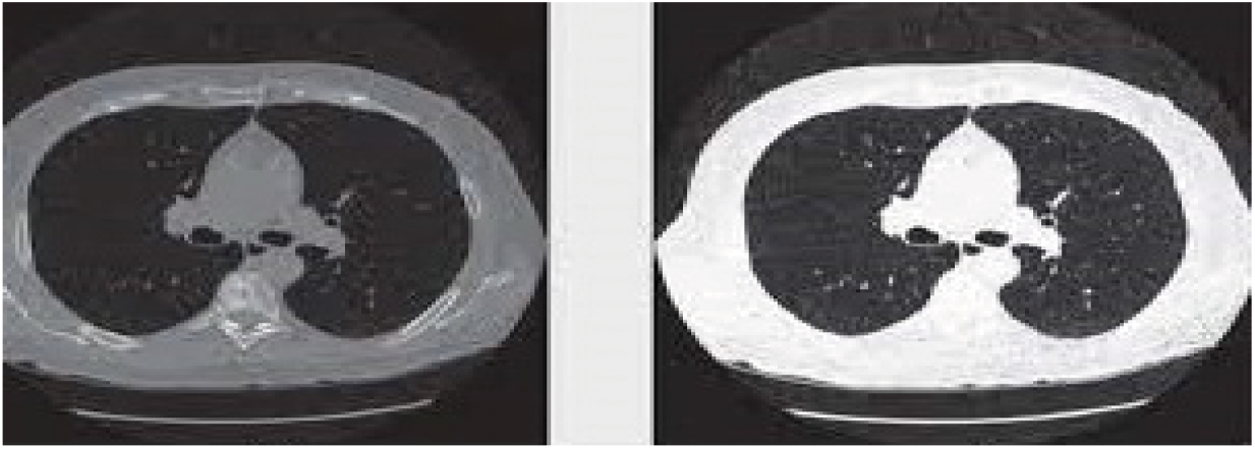

The medical preprocessing technique is used to remove noise pixels, low-quality pixels which affects the detection of lung cancers. Pixel Intensive testing process has been utilized to remove the inconsistent pixel and the noise pixels from the Input CT scan images. Also, Image histogram methods are adopted for enhancing the image quality because it works better on different images. Fig. 2 shows the preprocessed CT scan images after applying pixel classification and image histogram methods.

Figure 2: Sample preprocessed CT lung images